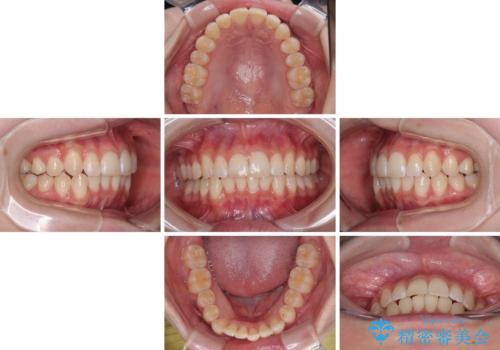

気になる前歯と咬み合わせを改善 インビザライン・モデレート

- 上下前歯の重なりを気にして来院された患者様です。

安価なインビザラインパッケージを用いての治療を希望されており、デコボコの程度が中等度であったため、インビザライン・モデレートを用いて矯正治療を行うこととしました。

インビザライン・モデレートは、製作できるアライナーの枚数に制限があるため、移動可能な量に限りがあるものの、インビザライン・ライトよりも枚数が多いため、幅広い症例に対応可能です。